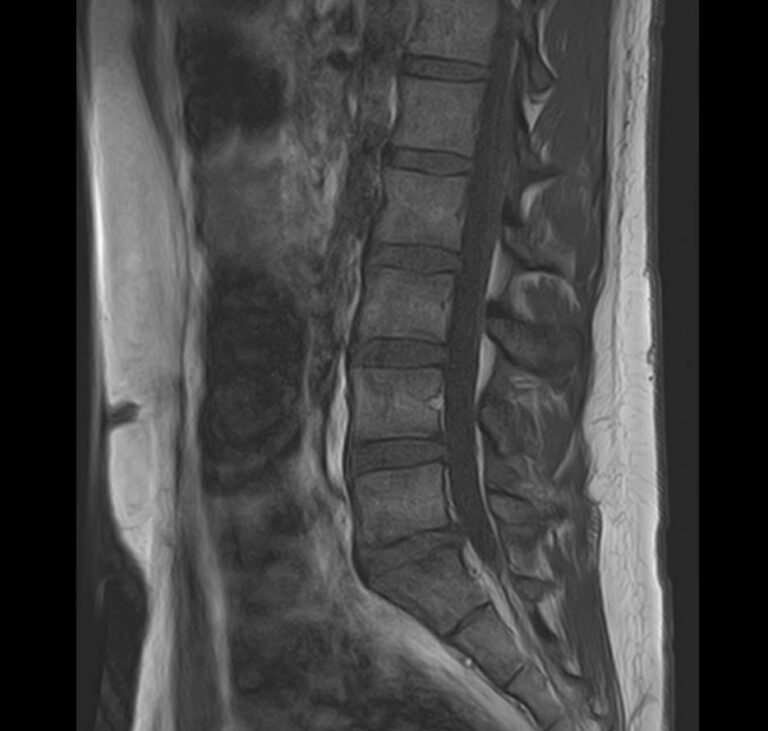

Боли в нижней части спины появляются на фоне различных заболеваний позвоночника, которые возникают при сочетанном поражении пояснично-крестцового отдела и крестцово-подвздошных сочленений.

Пояснично-крестцовый отдел позвоночника принимает на себя основной вес тела, поэтому поясничные позвонки отличаются массивным строением. Крестец образует единую кость за счет 5 сросшихся между собой позвонков и помогает поддерживать тело в вертикальном положении. Крестцово-подвздошное сочленение – крупный малоподвижный сустав, место соединения крестца и подвздошных костей. Эти анатомические области испытывают большие нагрузки и достаточно часто вовлекаются в патологический процесс при травмах, дегенеративных поражениях, инфекциях и опухолевых заболеваниях.

Наиболее точным и эффективным способом диагностики причин появления болей в нижней части спины является МРТ. С помощью данного метода можно оценить состояние всех анатомических структур позвоночного столба на исследуемом уровне, диагностировать поражение позвоночника на начальной стадии, когда другие методы не дают результатов. Такой патологией, в частности, является сакроилеит (воспаление крестцово-подвздошного сочленения), который часто становится причиной анкилоза (сращения) или нестабильности (патологической подвижности) сустава. Выявление сакроилеита на ранней стадии значительно улучшает прогноз в плане лечения и профилактики осложнений.

В клинике «Доступная медицина» диагностика патологии нижней части спины осуществляется на высокотехнологичном оборудовании – новейшем высокопольном томографе TOSHIBA VANTAGE TITAN 1,5 Тесла, который обеспечивает высочайшее качество изображений, точность и достоверность полученных данных. Магнитно-резонансная томография осуществляется без применения ионизирующего излучения, поэтому является безопасным методом обследования и может применяться неоднократно по мере необходимости.

Что можно диагностировать при проведении МРТ пояснично-крестцового отдела позвоночника + МРТ крестцово-подвздошных сочленений

При проведении данного комплексного обследования можно выявить:

• дегенеративно-дистрофические заболевания позвоночника: спондилез, спондилоартроз, остеохондроз;

• стеноз (сужение) позвоночного канала;

• грыжи межпозвонковых дисков (протрузии, экструзии);

• переломы позвонков, их смещение;

• спондилиты, гнойные артриты, сакроилеит, абсцессы околопозвоночных тканей и другие воспалительные заболевания, туберкулез;

• опухоли позвоночника и окружающих тканей;

• патологические изгибы позвоночника, сколиоз, усиленный или выпрямленный лордоз как нарушение статической функции позвоночника;

• аномалии строении позвоночника.